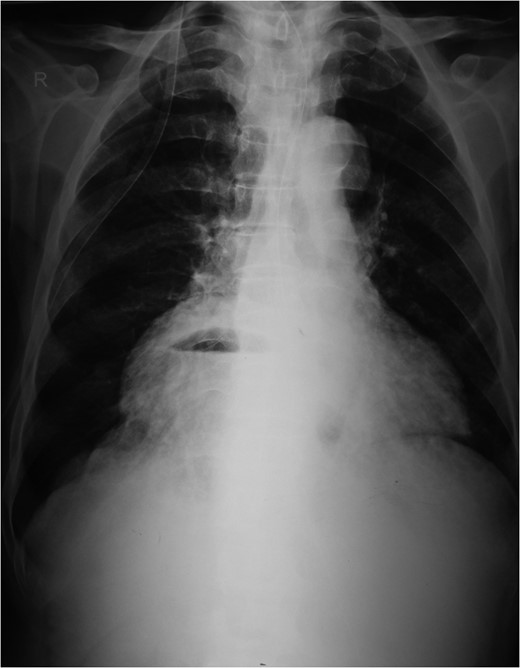

An 80-year-old man presented to our emergency room with multiple episodes of non-bilious vomiting for 4 days and not-passing stool or flatus for 2 days. He also complained of intermittent pain in the upper abdomen, which was not associated with fever, chest pain, melena or diarrhea in the recent past. However, he complained of increased cough and shortness of breath for the last 4 days on the background of a diagnosed chronic obstructive pulmonary disease. There were no similar complaints in the past. On examination, his vital parameters were normal, other than an oxygen saturation of 82% for which oxygen had to be given via face mask. His abdominal examination revealed epigastric fullness with tenderness in the epigastric and right hypochondrium. There was no evidence of peritonitis. Laboratory investigations revealed hypokalemia (3.1 mEq/l) with other parameters being normal. On the chest X-ray obtained, we saw air–fluid levels in the right thoracic cavity (Fig. 1). Computed tomography (CT) scan of the abdomen performed demonstrated a right anterior diaphragmatic hernia with stomach as content. (Figs 2 and 3) The patient was taken to the operating room, and an upper midline laparotomy was performed. Findings included an ~4 × 3 cm defect to the right of the sternum in the anterior diaphragm (Fig. 4), with incarcerated pylorus/antrum of stomach as contents and a grossly distended stomach. Rest of the bowel was normal. The contents were reduced, and the defect closed primarily with 2-0 non-absorbable interrupted mattress sutures (Fig. 5). Postoperative period was uneventful, and chest X-ray revealed a corrected defect with reduced contents (Fig. 6). The patient was started orally on the first postoperative day and discharged on the sixth postoperative day.

Diagnosis is usually suggested by chest X-rays indicating an air–fluid level in the chest with Barium studies revealing contrast in the stomach/bowel herniating through the diaphragm. CT scan of the chest and diaphragm are highly accurate and help proceed with surgical management [7].